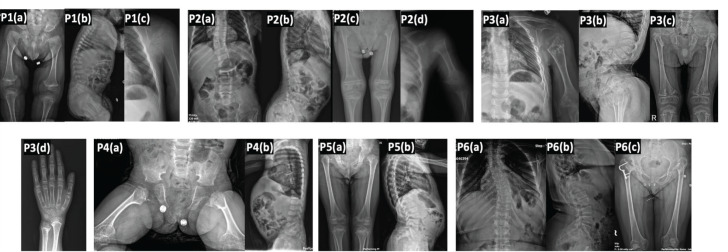

Methods: Six patients from five unrelated families presented with disproportionate short stature.delayed motor milestones, waddling gait, normal intelligence, and similar radiological features, including delayed epiphyseal ossification, epimetaphyseal changes, scoliosis, lordosis, and platyspondyly. All underwent whole exome sequencing. Demographic, clinical, laboratory, and radiological data were retrospectively obtained from hospital records. Segregation analysis was conducted using Sanger sequencing in all patients.

Results: Based on clinical, radiological, and molecular results, the six patients were categorized into kniest dysplasia, spondyloepiphyseal dysplasia congenita, and spondyloepimetaphyseal dysplasia Strudwick type. Four novel variants (c.1023+2T>C, p.Gly465Asp, p.Gly855Asp, p.Gly669Ala) were identified in the COL2A1 gene.